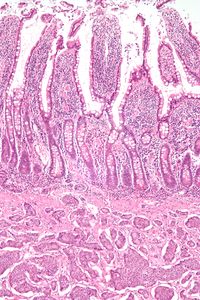

| Micrograph of a neuroendocrine tumor. H&E stain | |